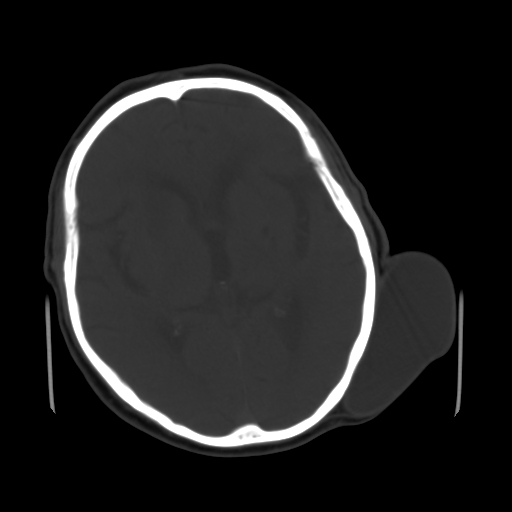

男,62岁,右侧肢体活动障碍不灵活三天,左侧头皮肿物十余年(ct值8hu)。

1)多发性腔隙性脑梗塞。2)脑白质病。3)脑萎缩。4)左侧枕顶部头皮下皮样囊肿,不排除脂肪瘤。

1)多发性腔隙性脑梗塞。2)脑白质病。3)脑萎缩。4)左侧枕顶部头皮下皮样囊肿或表皮样囊肿。